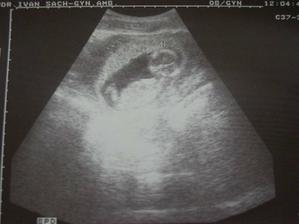

SRPŇÁTKA 2007 - fotky UTZ

album věnované mimískům, které se narodí v srpnu 2007 a jejich maminkám ze "Společného termínu SRPEN"